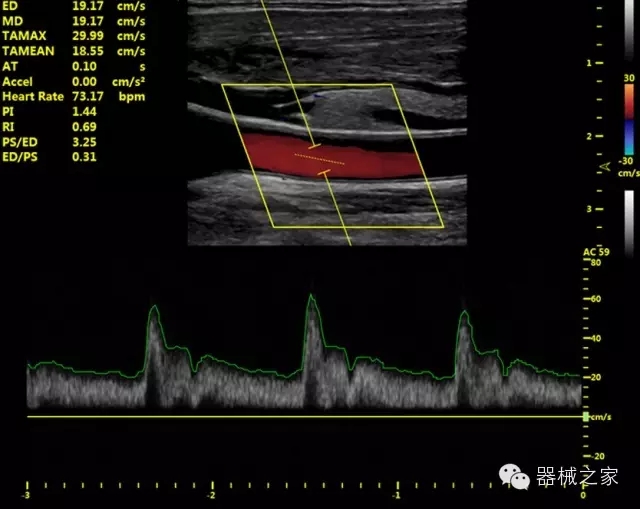

產(chǎn)品特點(diǎn)

·全球目前唯一一款配備主機(jī)雙探頭接口,整機(jī)重量(含電池)在5公斤以內(nèi)的便攜式彩超;

·一款互聯(lián)網(wǎng)彩超,只要有手機(jī)信號的地方就可以非常方便地實(shí)現(xiàn)遠(yuǎn)程會(huì)診和病案調(diào)?。?/span>

·獨(dú)有的HoloTM PW 實(shí)時(shí)3取樣門PW成像技術(shù),精確進(jìn)行血管診斷;

·一鍵優(yōu)化B、Color、PW,Auto Doppler自動(dòng)識別血管位置、偏轉(zhuǎn)角度等,提高工作效率;

·30°超廣角精細(xì)偏轉(zhuǎn)成像技術(shù),更優(yōu)異的頻譜圖像;